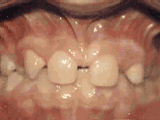

牙列稀疏,牙槽骨過長,或者牙齒少,導(dǎo)致排列太寬松,零零散散,經(jīng)過矯正后的是這樣的~

牙列稀疏,牙槽骨過長,或者牙齒少,光頭強(qiáng)就是這類。導(dǎo)致排列太寬松,零零散散,經(jīng)過矯正后的是這樣的~